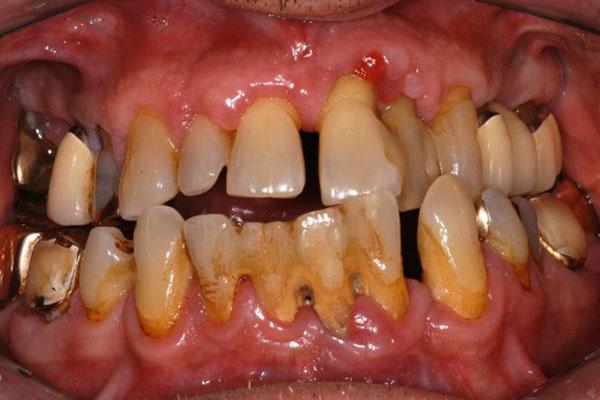

Qeyri-cərrahi parodontoloji müalicədən sonra bəzi hallarda, bu və ya digər bölgədə dərin parodontal ciblər (diş əti və sümük cibi) qalmaqda davam edir. Bu hallarda çox zaman müalicə cərrahi metodların tətbiqi ilə davam etdirilir. Bu zaman əsas məqsəd mövcud parodontal cibin bu və ya digər metodlarda aradan qaldırılmasını təmin etməkdir.

Çünki bu ciblər çox zaman pasiyent tərəfindən yetərincə təmizlənə bilmir. Bu isə həmin bölgəyə tədricən ərp və dolayısı ilə də bakteriya koloniyalarının toplanmasına səbəb olur. Bu proses yenidən yerli iltihabın ortaya çıxmasına səbəb olur. Tətbiq edilən cərrahi metodlar əsasən cibin yerləşdiyi diş bölgəsi, cibin eni, dərinliyi, konfiqurasiyası və s. xüsusiyyətlərə görə müəyyənləşdirilir. Bu zaman məqsəd mümkün olduqda həmin bölgədə bərpa prosedurunu həyata keçirmək, mümkün olmadıqda isə rezektiv müalicənin tətbiqi ilə həmin bölgəyə ərp toplanma ehtimalını azaltmaq və gigiyenik prosedurların icrasını pasiyent üçün rahatlaşdırmaqdır.